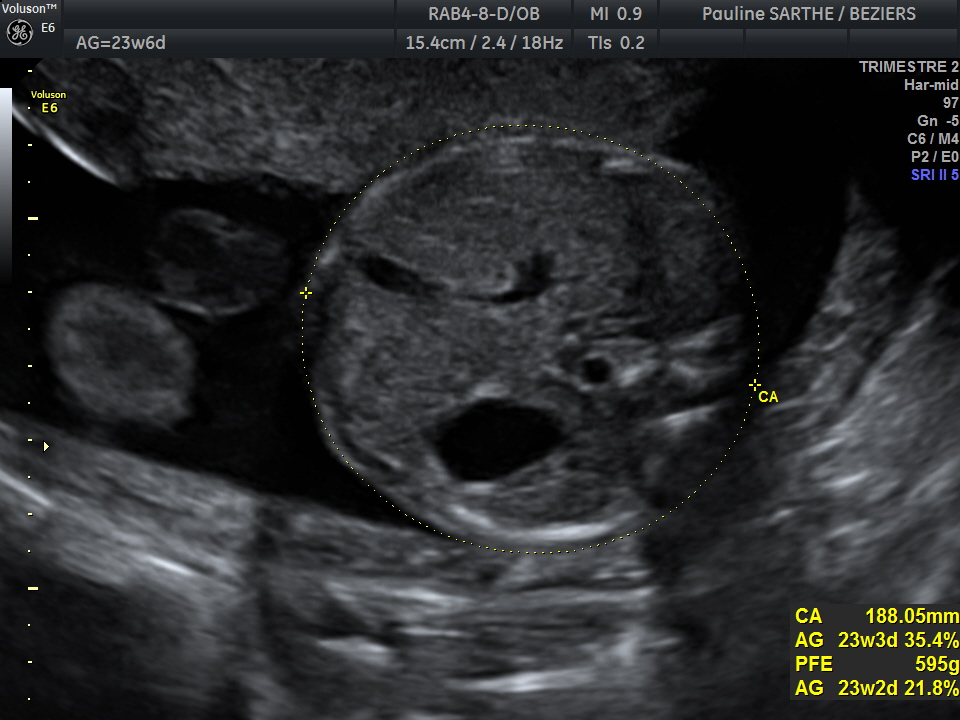

- l'échographie du 2 ème trimestre est réalisée entre 20 et 24 semaines d'aménorrhées (idéalement entre 21-23 semaines).Votre bébé a bien grandi et il est difficile de le visualiser en entier. C'est le moment idéal pour bien vérifier la vitalité de votre bébé à travers ses mouvements et le liquide amniotique , le bon développement de ses organes, sa croissance au travers des mesures de sa tête, de son périmètre abdominale et de son fémur qui permettront de donner une estimation de son poids ,et la localisation du placenta.

Parfois, si votre gynécologue ou votre sage-femme le demande , il peut être nécessaire d'effectuer une mesure du col. L’examen peut-être complété par des Dopplers analysant la bonne circulation du sang au niveau du cordon ombilical et des artères utérines.